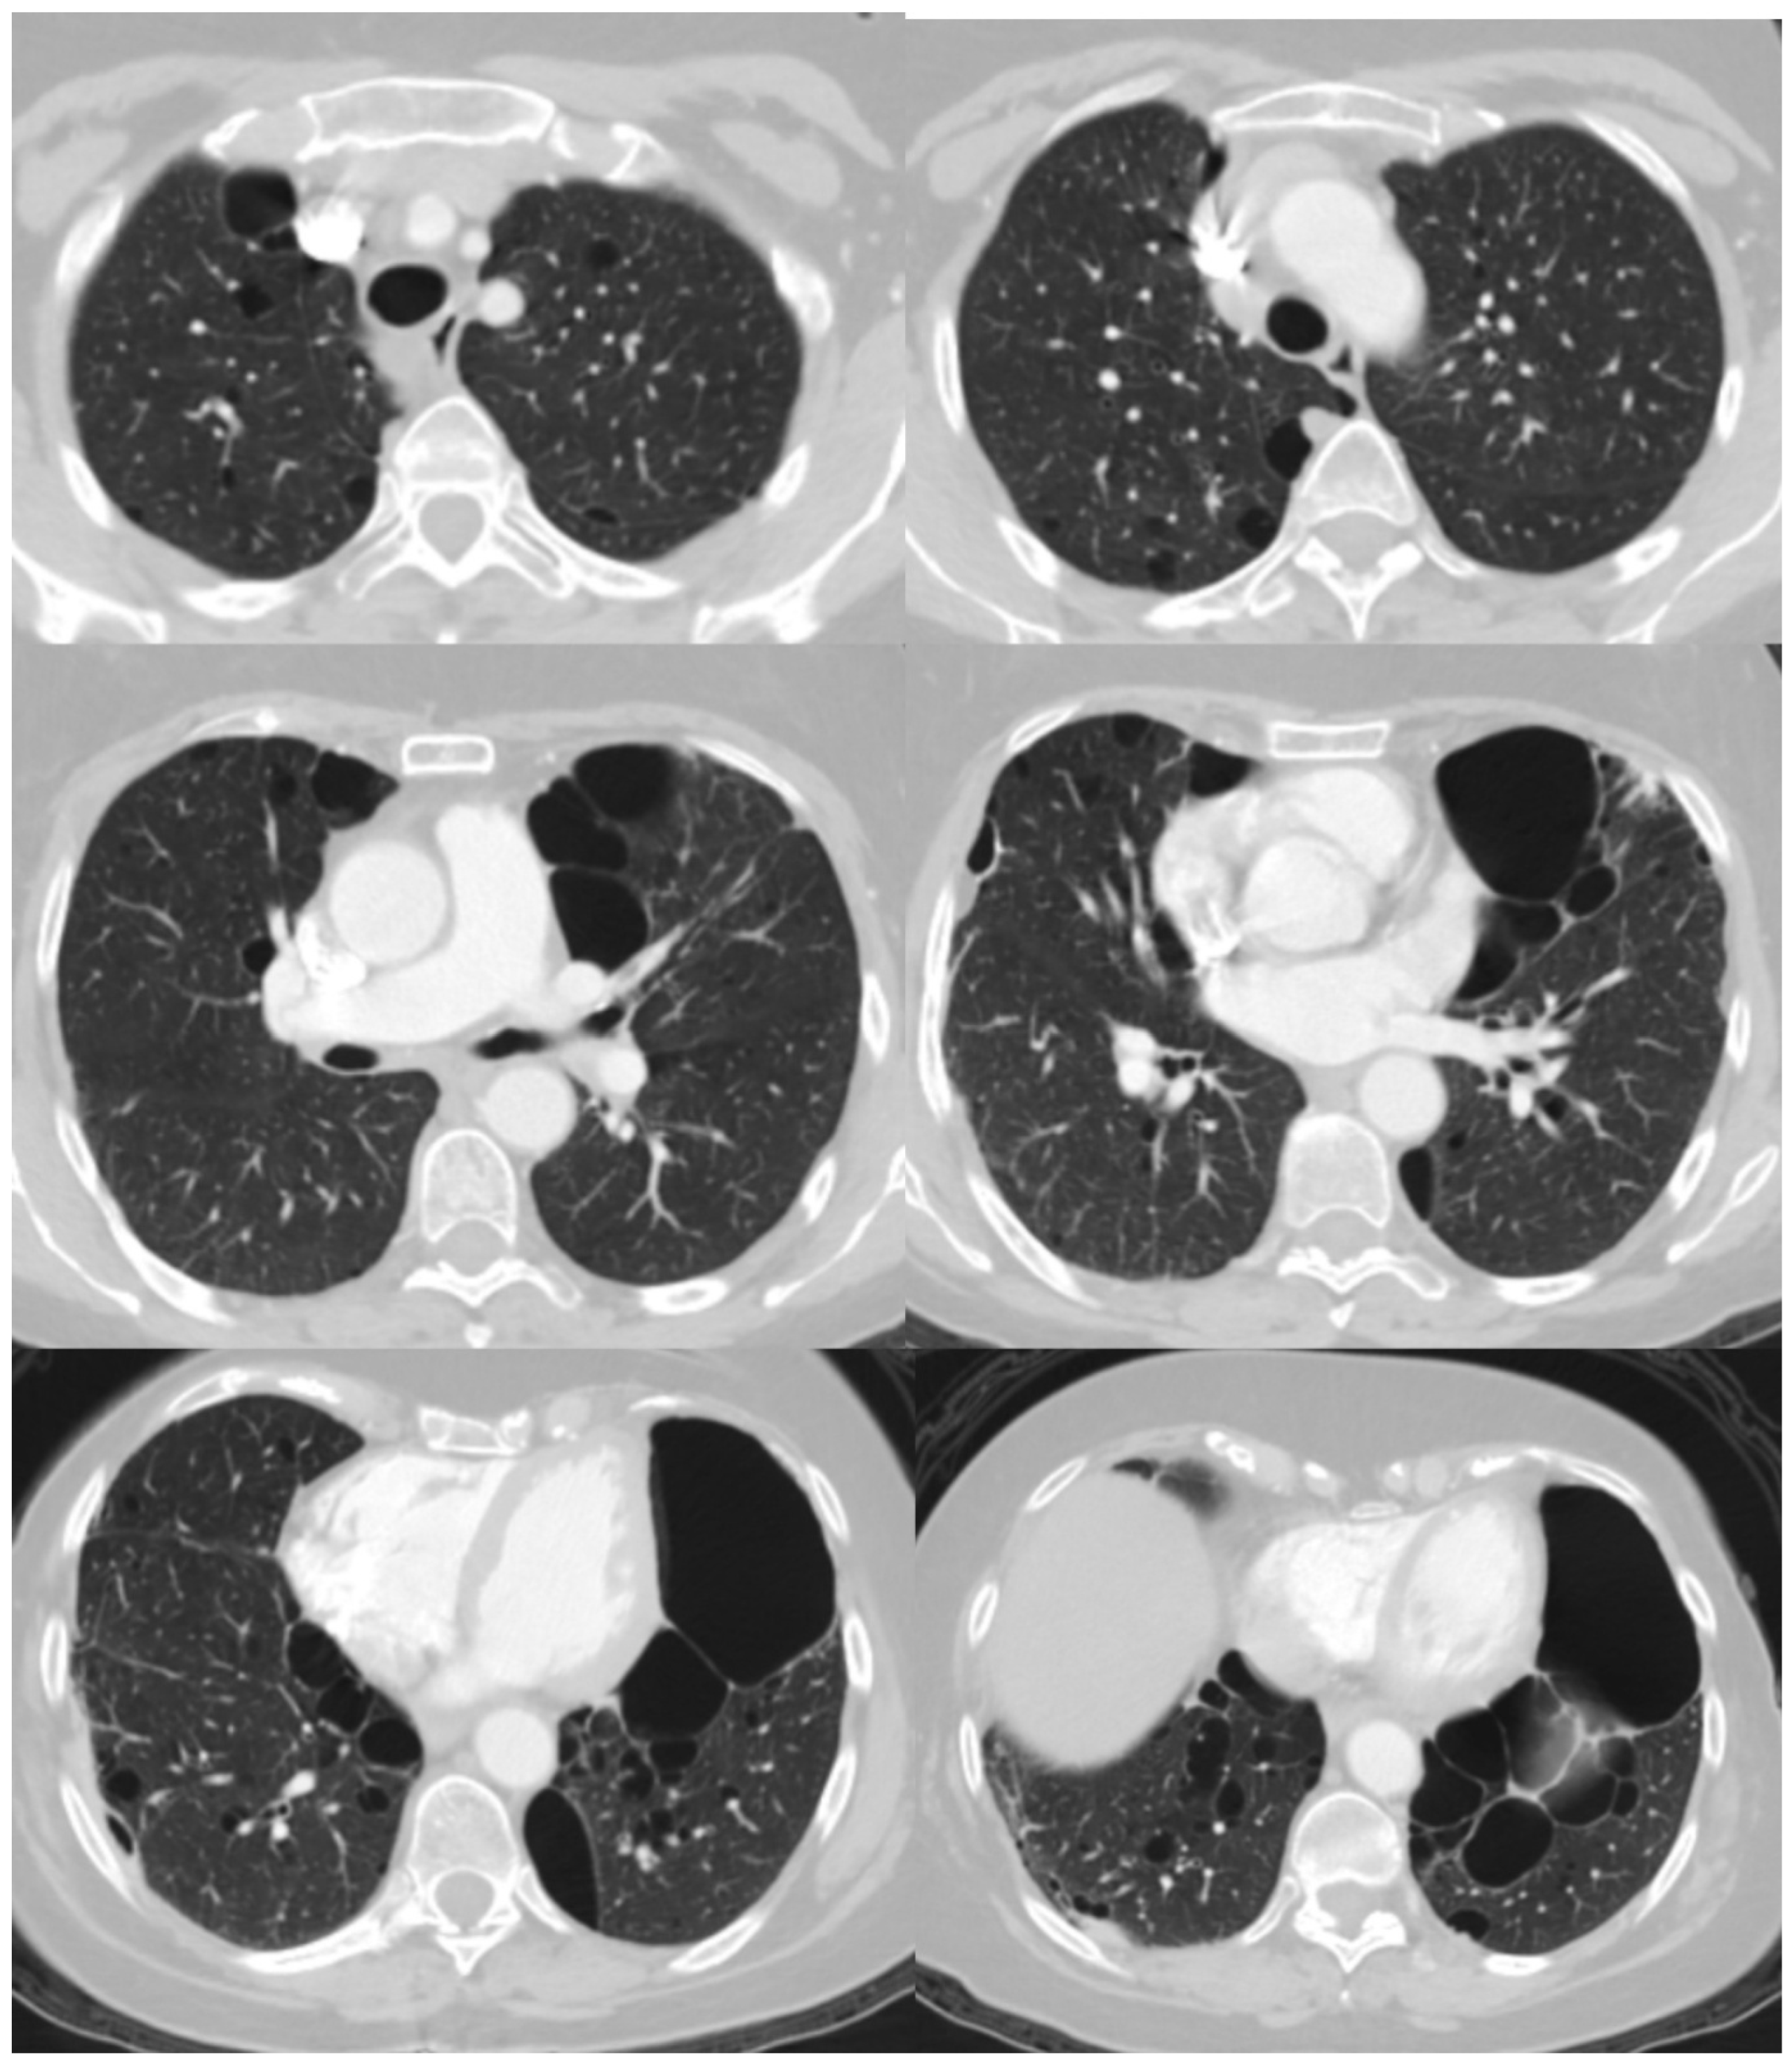

5.4. Radiological Features

- Agarwal, P.P.; Gross, B.H.; Holloway, B.J.; Seely, J.; Stark, P.; Kazerooni, E.A. Thoracic CT Findings in Birt-Hogg-Dube Syndrome. AJR Am. J. Roentgenol. 2011, 196, 349–352. [Google Scholar] [CrossRef]

- Lee, J.E.; Cha, Y.K.; Kim, J.S.; Choi, J.H. Birt-Hogg-Dubé Syndrome: Characteristic CT Findings Differentiating It from Other Diffuse Cystic Lung Diseases. Diagn. Interv. Radiol. 2017, 23, 354–359. [Google Scholar] [CrossRef] [PubMed]